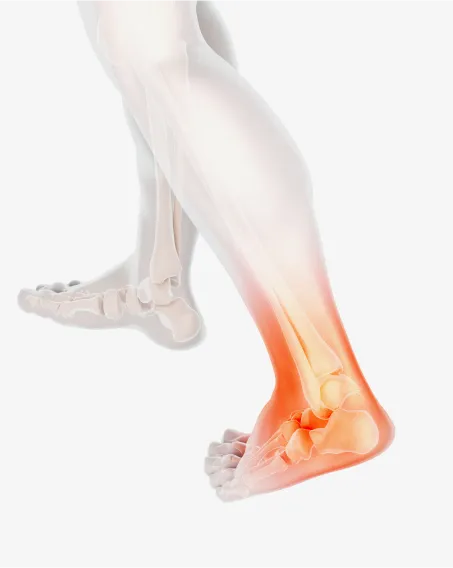

발에서 악! 소리나면 몸에서 억! 소리난다.

발의 문제는 전신통증의 시작입니다.

발은 우리 몸에서 건물의 주춧돌과 같은 역할을 합니다. 발의 틀어짐으로 인한 통증은 단순히 발의 문제로 그치지 않고 보행 패턴을 무너뜨리며 다리와 무릎 관절, 나아가 골반과 허리의 추간판까지 연쇄적인 영향을 미칩니다. 발의 문제를 조기에 발견해 치료하는 것이 전신 건강을 위해 중요합니다.